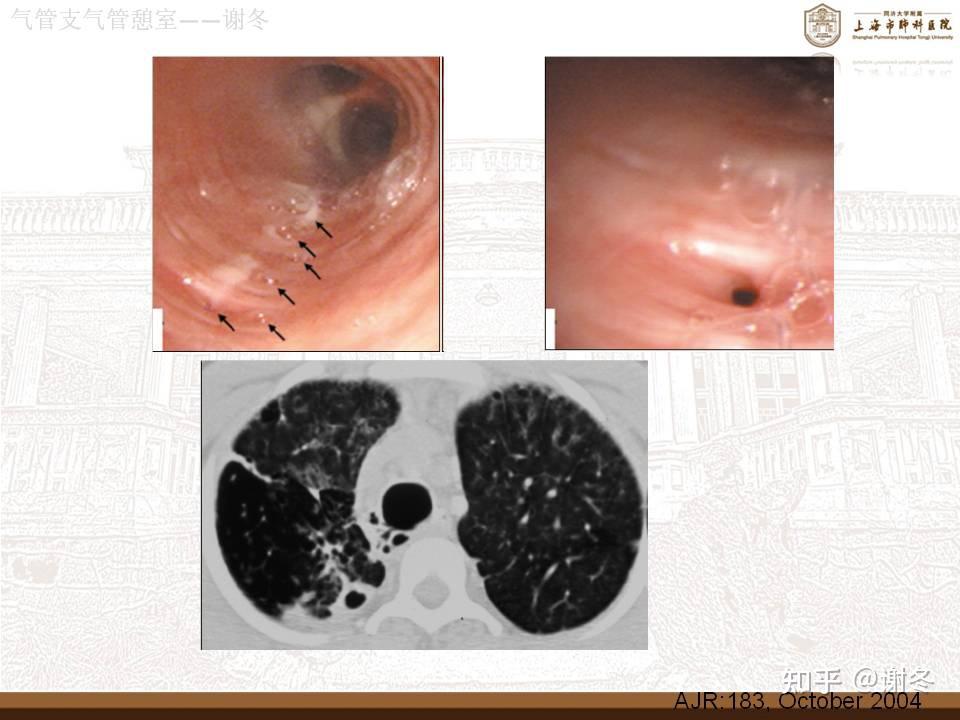

气管,支气管憩室

气管憩室与气管性支气管